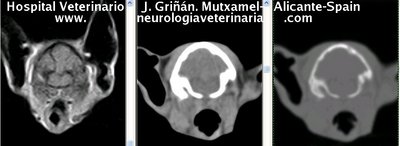

Se muestran cortes transversales de Resonancia Magnética (imagen a la izqda del lector), TC contrastado para tejidos blandos (imagen del centro) y TC contrastado para tejidos duros (imagen de la derecha del lector).

Nótese como la Resonancia supera al TC en el contraste de tejidos blandos (encéfalo y médula espinal) y en el de líquidos (ojo y líquido cefalorraquídeo), mientras que el TC supera a la resonancia en el contraste de tejidos duros (hueso) y aire (senos, cavidad nasal y bullas)